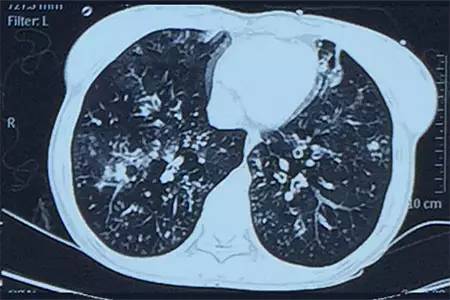

肺CT見(jiàn)下圖

該患者肺部影像學(xué)表現(xiàn)為明顯的支氣管擴(kuò)張,同時(shí)伴有彌漫的滲出斑片影���,考慮合并感染���,細(xì)菌學(xué)培養(yǎng)提示為綠膿桿菌,結(jié)合藥敏結(jié)果給予頭孢他啶+阿米卡星抗感染���,患者存在II型呼吸衰竭予氣管插管機(jī)械通氣支持���,加強(qiáng)體位引流排痰,治療18天���,患者情況好轉(zhuǎn)出院���。